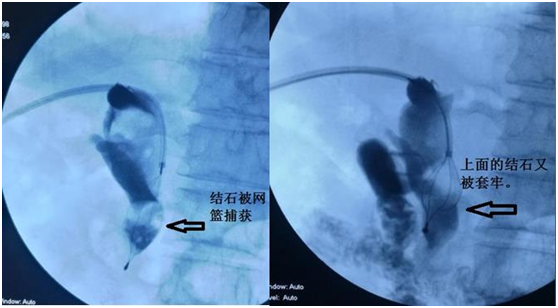

因结石比较巨大,因此治疗起来比较困难,两块结石上下重叠,给抓捕带来困难。首先先使两块石头分离,逐个将其抓捕并粉碎。其次再将粉碎的结石推入肠道,又因为患者以前做过手术,胆总管远端粘连狭窄,结石只有粉碎到足够小才能被推到肠道,又给手术增加了难度。朱亮副主任医师、王宏学主治医师联合应用多种介入技术,将结石推入肠道,术后患者恢复良好,得到了患者及家属的高度评价。